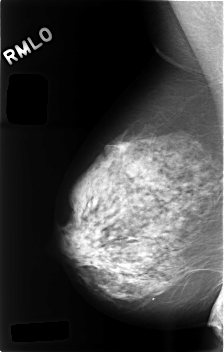

C_0495_1.RIGHT_MLO

RIGHT_MLO LINES 4576 PIXELS_PER_LINE 2912 BITS_PER_PIXEL 12 RESOLUTION 50 NON_OVERLAY